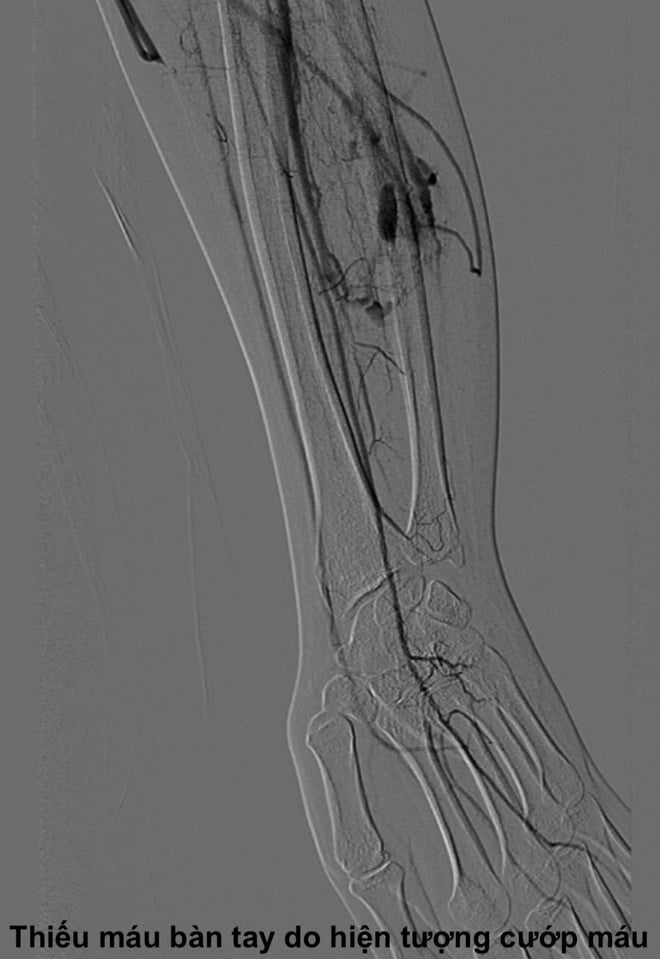

លោកវេជ្ជបណ្ឌិត Cuong បានពន្យល់ថា លំហូរឈាមដែលមានល្បឿនលឿនដែលឆ្លងកាត់ការខូចទ្រង់ទ្រាយនេះនឹងមិនអាចផ្តល់អុកស៊ីហ្សែន និងសារធាតុចិញ្ចឹមដល់ជាលិកានៅខាងក្រោមចរន្តបានទាន់ពេលវេលានោះទេ។ នេះនាំឱ្យមាន "បាតុភូតលួច" ដែលក្នុងនោះការខូចទ្រង់ទ្រាយបូមឈាមពីសរសៃឈាមធម្មតាដែលនៅក្បែរនោះធ្វើឱ្យម្រាមដៃឬអវយវៈទទួលរងនូវជំងឺ ischemia រ៉ាំរ៉ៃ។ នេះគឺជាមូលហេតុនៃរោគសញ្ញានៃការឈឺចាប់ ស្ពឹក ហើម កំដៅ ឬសូម្បីតែការខូចទ្រង់ទ្រាយនៃអវយវៈរបស់អ្នកជំងឺ។

ប្រសិនបើមិនបានព្យាបាលទេ ស្ថានភាពនេះអាចនាំឱ្យមានផលវិបាកធ្ងន់ធ្ងរ។ យូរៗទៅ សរសៃឈាមនៅកន្លែងខូចទ្រង់ទ្រាយអាចរីកធំ ធ្វើឱ្យជញ្ជាំងសរសៃឈាមចុះខ្សោយ និងបណ្តាលឱ្យហូរឈាមច្រើន។ ប្រសិនបើការខូចទ្រង់ទ្រាយធំពេក បេះដូងនឹងត្រូវធ្វើការខ្លាំងពេកដើម្បីបូមឈាម ដែលនាំឱ្យមានជំងឺខ្សោយបេះដូង ។